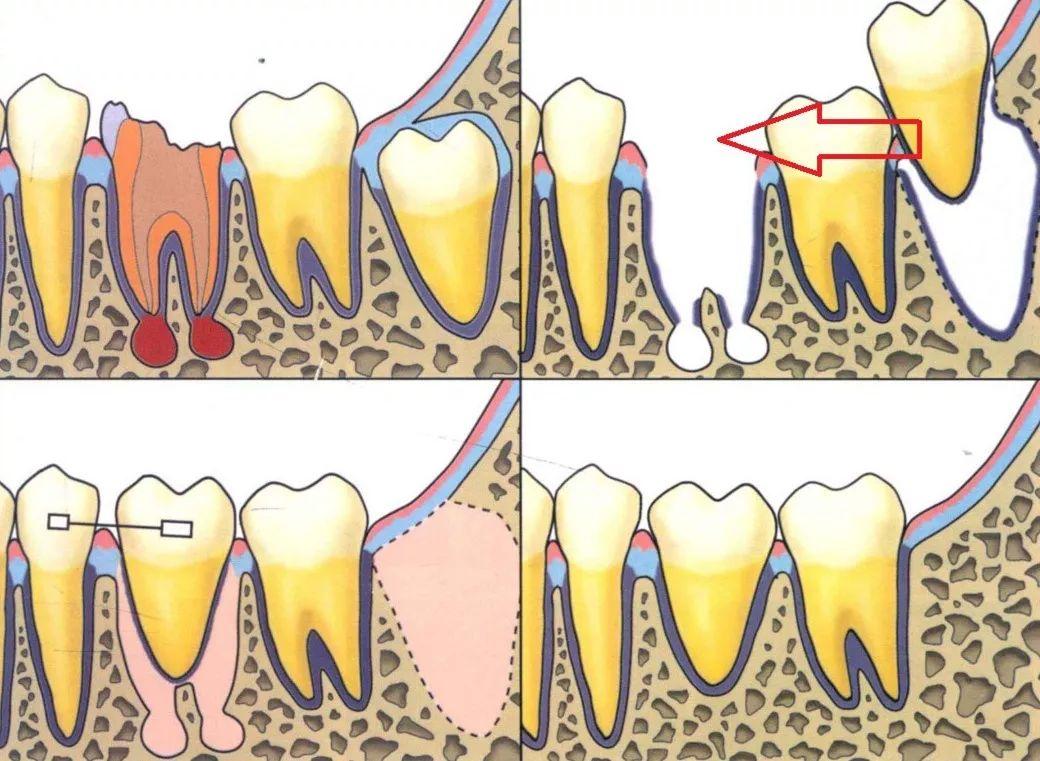

一、自体牙移植是什么?自体牙移植是指:将患者自身的埋伏牙、阻生智齿、错位牙或多生牙由一个位置移植到另一个位置,以代替坏牙行使功能。

利用没有功能的阻生智齿来代替不能保留的患牙:把阻生的智齿和严重龋坏不能保留的患牙同时拔除,再将完好的智齿移植到患牙的牙槽窝内,通过机体自身愈合机制,智齿与牙槽骨能良好的结合,进而替代被拔除的患牙,行使功能,即大限度的保留了天然牙,又避免了种植牙,给患者多一种的选择。

(自体牙移植示意图)